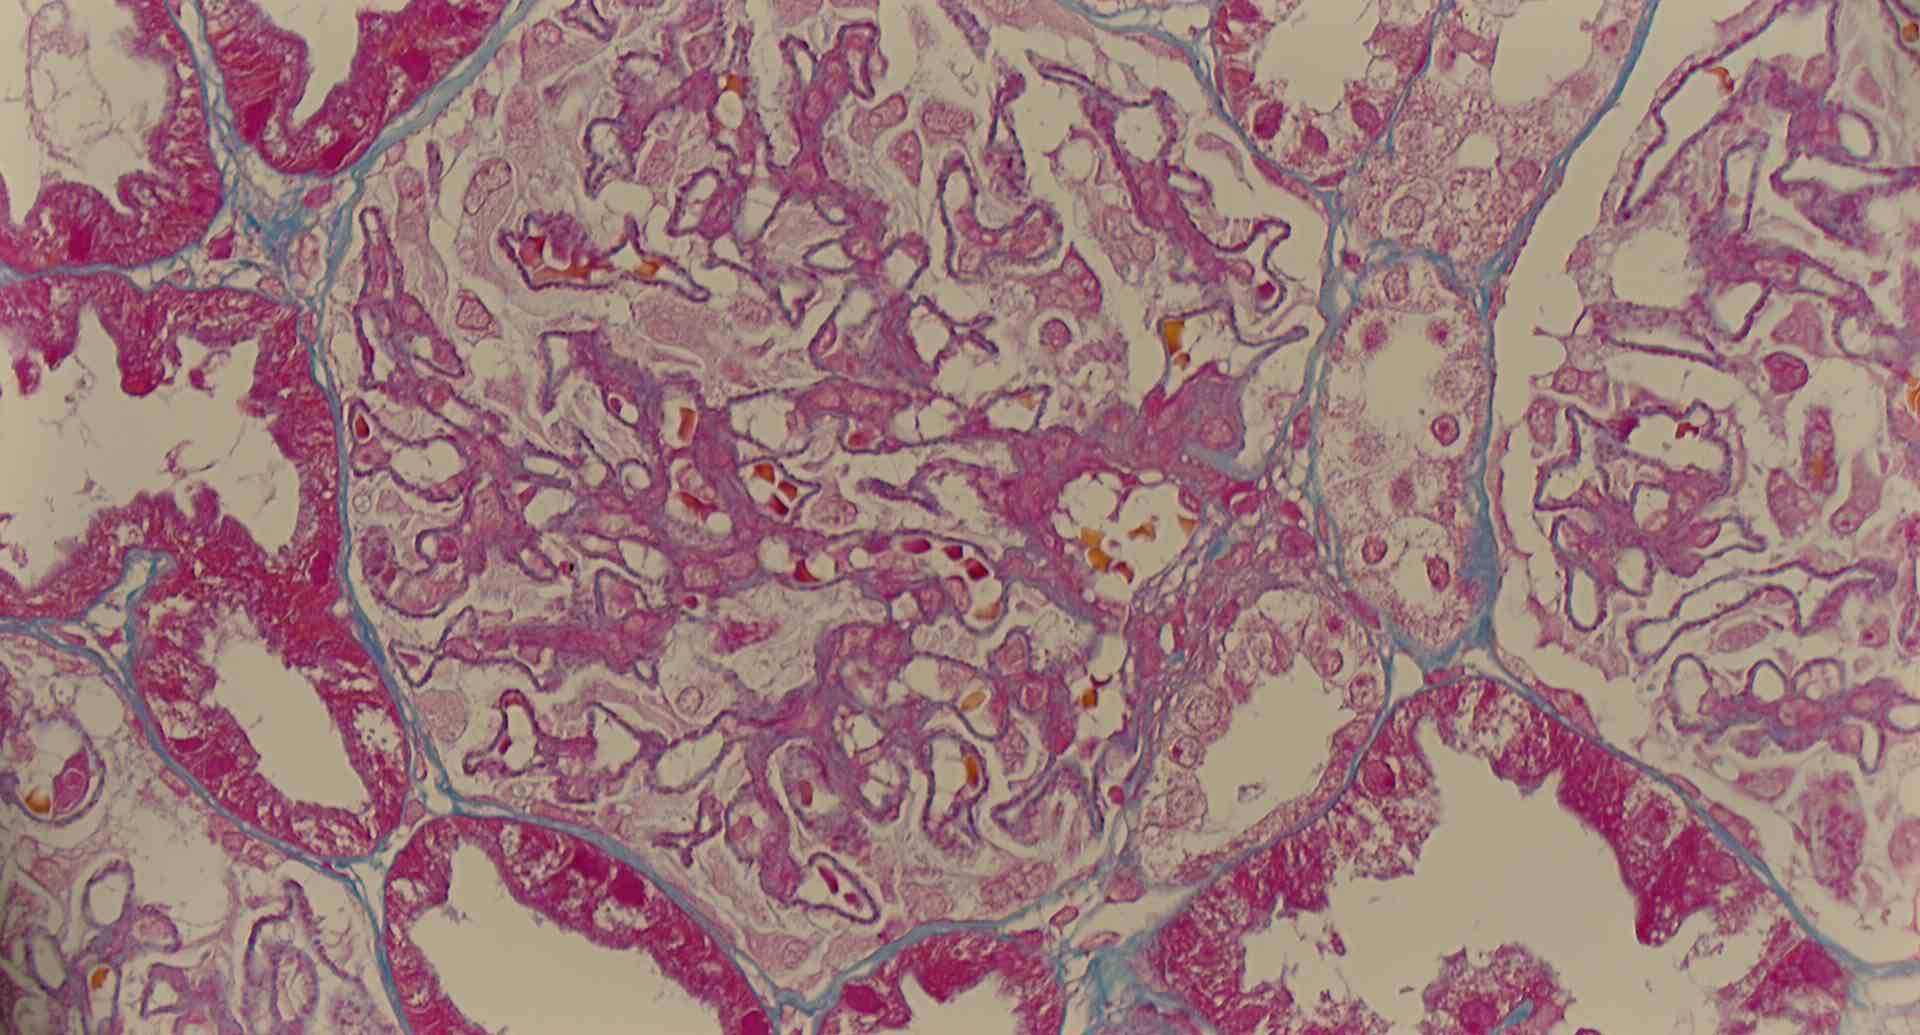

標本の説明

標本15